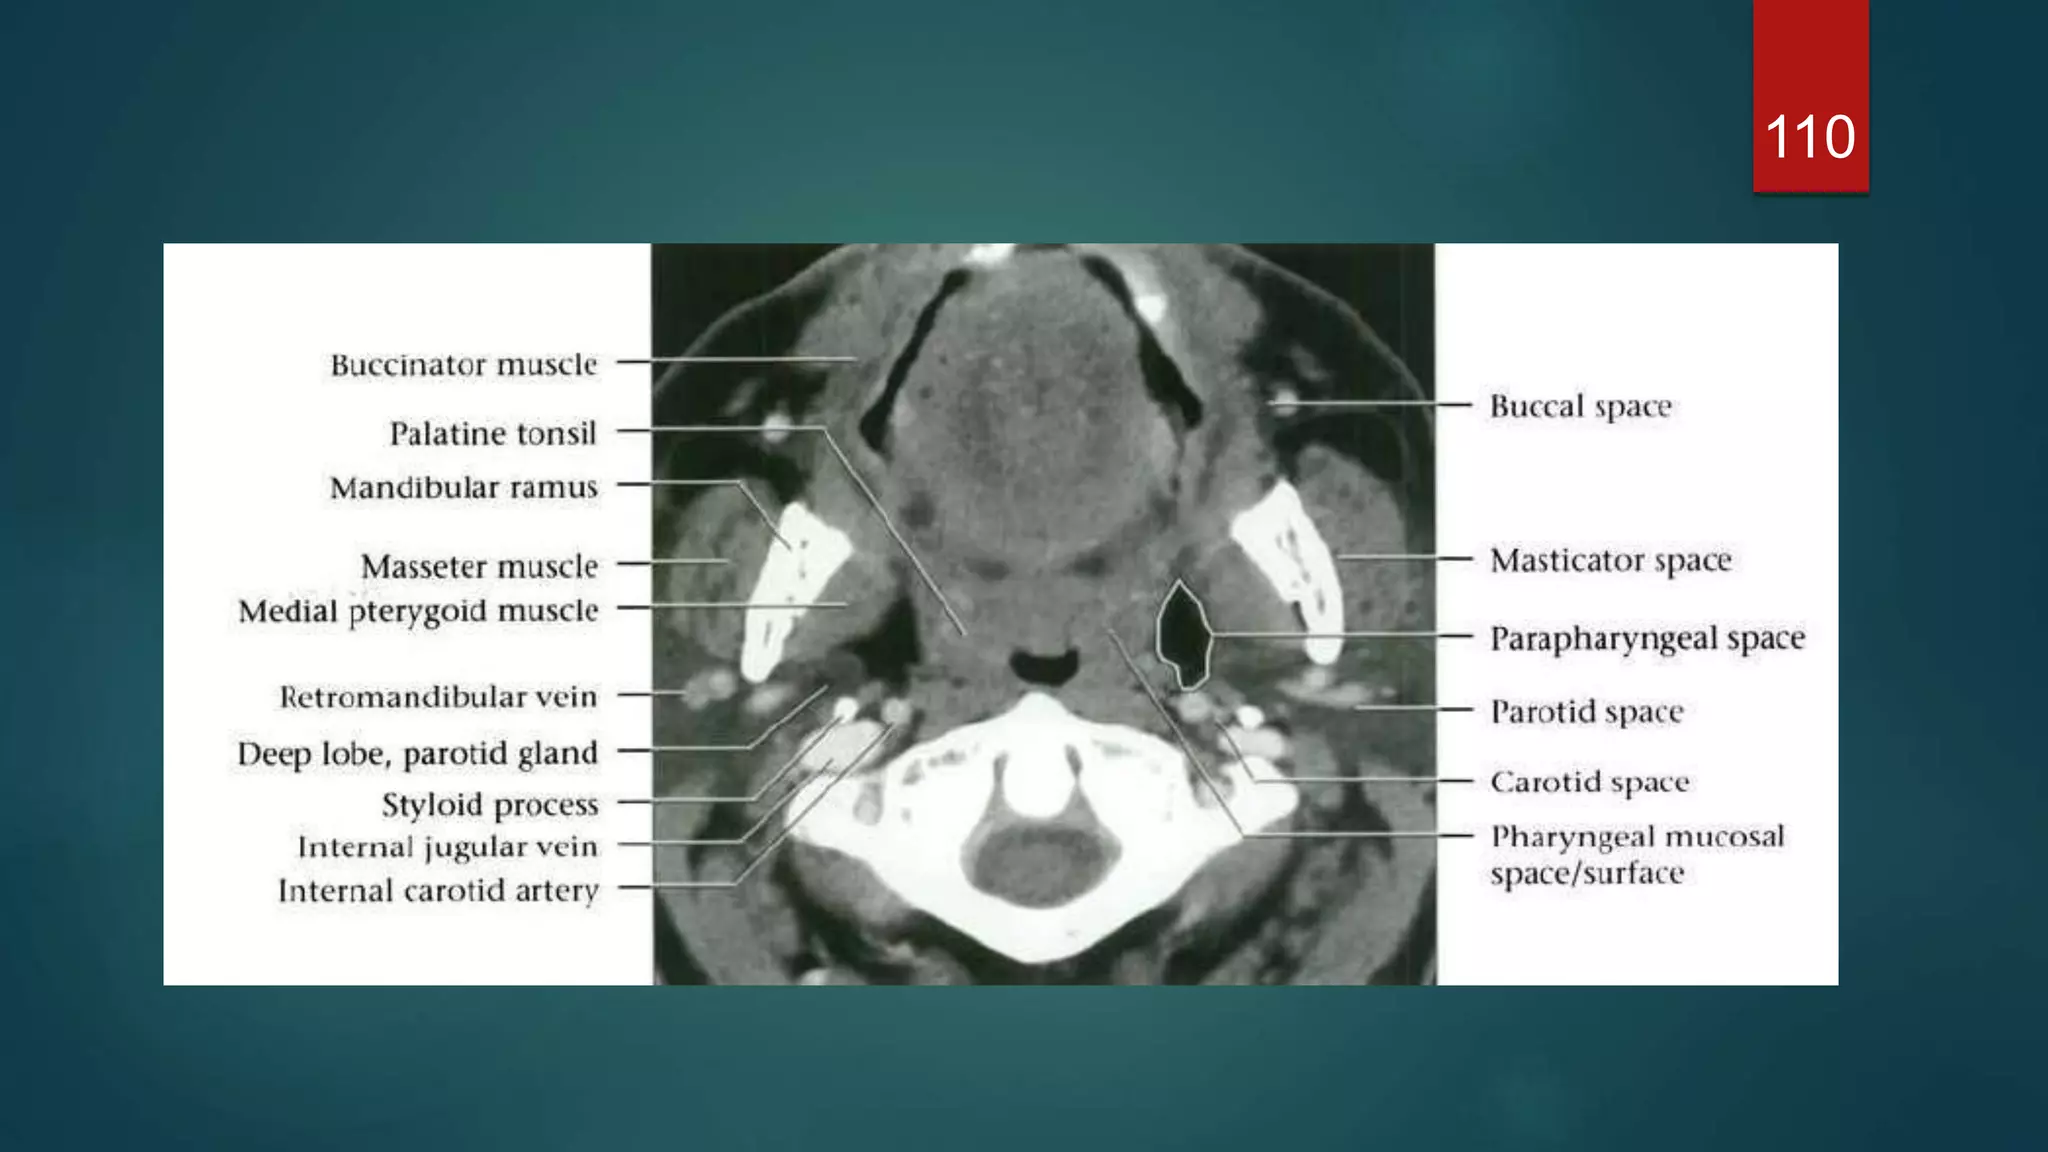

CT

109

110